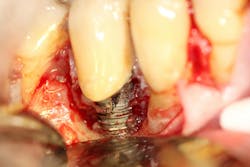

Gum recession around dental implants due to craniofacial development is a significant concern in implant dentistry, with the potential to undermine both the esthetic and functional success of dental implant procedures. When the gum tissue surrounding the implant site begins to recede, it can expose the underlying adjacent tooth root or the surface of the dental implant itself (figure 5). This not only affects the natural appearance of the artificial tooth but also increases the risk of dental implant failure and other complications.

For patients who already exhibit signs of gum recession around their dental implants, advanced treatments such as bone grafting may be necessary to restore the supporting bone and stabilize the implant (figure 6). Addressing the underlying causes—such as correcting poor oral hygiene habits, managing teeth grinding, and treating existing gum disease—is critical to prevent recurrence and ensure the longevity of the implant.